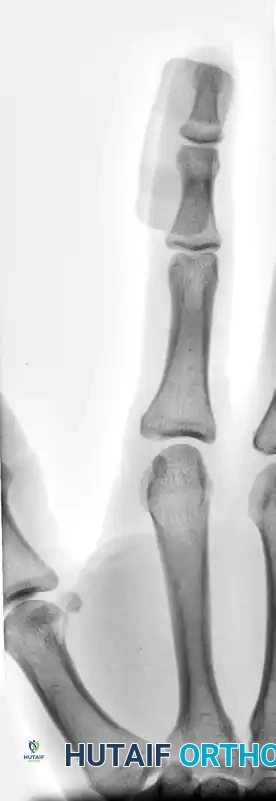

These injuries involve a closed disruption of the terminal extensor tendon, often presenting with secondary "swan neck" posturing of the proximal interphalangeal (PIP) joint due to proximal retraction of the extensor mechanism.

FIGURE 67-65 A: Acute type 1 mallet finger demonstrating the classic flexion deformity at the DIP joint with secondary “swanning” (hyperextension) of the proximal interphalangeal joint.